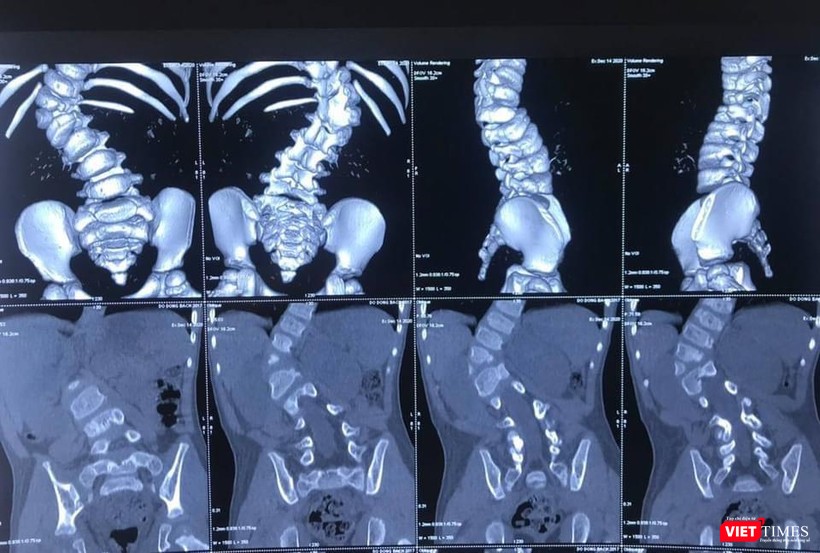

Năm nay bé 3 tuổi, tình trạng biến dạng cột sống của bệnh nhi B.Đ đã là mức độ nặng, góc vẹo 66 độ. BS chuyên khoa chẩn đoán cho biết nếu trì hoãn mổ, đến khi bệnh nhi được 6 tuổi trở lên thì sẽ không thể phẫu thuật nắn chỉnh được dị tật vẹo cột sống, nguy cơ bệnh nhi sẽ mất đi cả cuộc sống bình thường. Vi thế, bố mẹ bé đã quyết định đưa bé nhập viện vào khoa Chấn thương - Chỉnh hình Cột sống (Bệnh viện 108).

Bác sĩ chuyên khoa cho biết vẹo cột sống bẩm sinh là biến dạng vẹo của cột sống do sự phát triển bất thường của cột sống ngay từ khi trẻ em sinh ra. Hai nguyên nhân chính của vẹo cột sống bẩm sinh là bất thường về sự phân chia đốt sống, bất thường về hình thành đốt sống hoặc kết hợp cả hai nguyên nhân. Mức độ tiến triển biến dạng gù vẹo cột sống rất dao động tùy theo vị trí đốt sống phát triển bất thường. Một số trẻ có đường cong vẹo ổn định và không thay đổi theo thời gian, trong khi đó có trẻ em biến dạng vẹo tiến triển không ngừng.

| Hình ảnh X quang ca cong vẹo cột sống của bệnh nhi 3 tuổi (BVCC) |

Về mặt phẫu thuật, đây là trường hợp cháu bé còn rất nhỏ tuổi nhưng đã có biến dạng cột sống rất lớn, góc vẹo cột sống T11-L2 66 độ, có dị tật nửa thân đốt L1 bên phải, thiểu sản cuống sống T12 bên phải. Do vậy, tính chất cuộc phẫu thuật rất phức tạp.